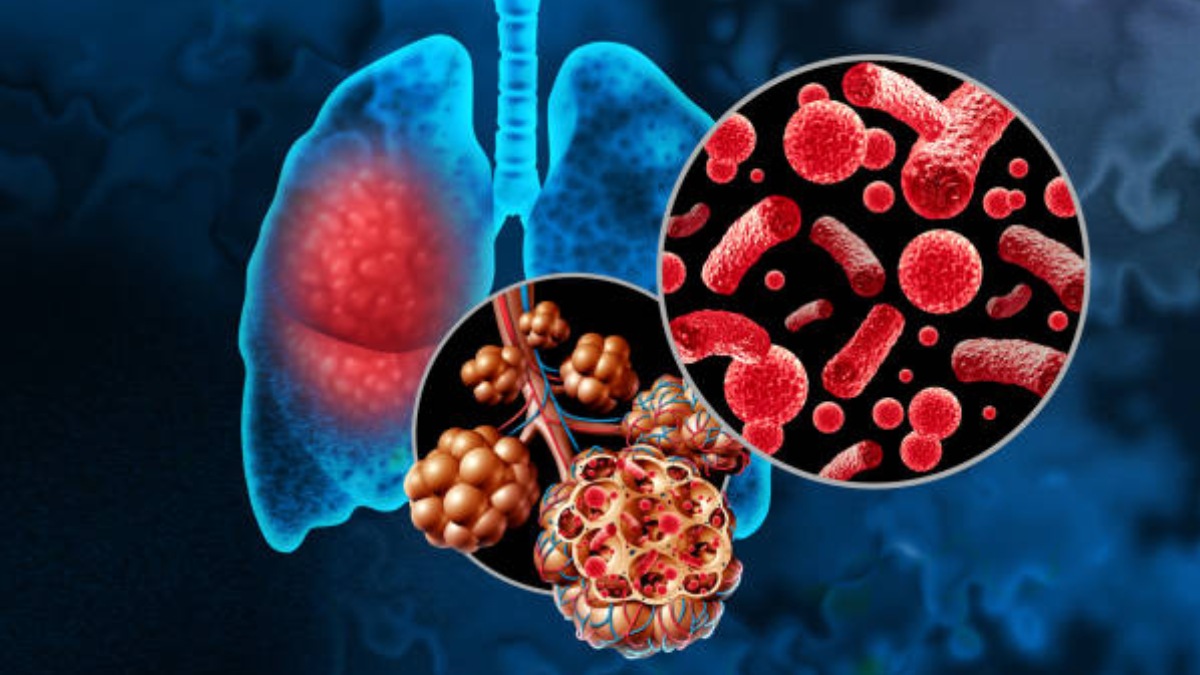

చలికాలంలో సాధారణంగానే పలు వ్యాధుల బారిన పడుతుంటాం. అందులో ముఖ్యమైనది న్యూమోనియా. ఇది ఒక రకమైన ఇన్ఫెక్షన్. ఇది బ్యాక్టీరియా, శిలింద్రాలు, వైరస్ల వల్ల వస్తుంది. ఈ వ్యాధి కారణంగా శ్వాసకోశ సంబంధిత సమస్యలు, చాతి నొప్పి వంటి సమస్యలు వస్తాయి. పిల్లలు, వృద్ధులను ఈ వ్యాధి అమితంగా ప్రభావితం చేస్తుంది. ఒక్కోసారి ఇది ప్రాణాంతకంగా కూడా మారుతుంది.

ఈ న్యూమోనియా ఊపిరితిత్తులను వాపుకు గురి చేస్తాయి. అలాగే ఊపిరి తిత్తుల్లో శ్లేష్మం, ద్రవం నిండిపోయేలా చేస్తుంది. ఇది శ్వాసను తీసుకోవడాన్ని నిలిపివేసి శరీరంలో ఆక్సిజన్ శాతాన్ని తగ్గిస్తుంది. క్రమంగా మనిషి చనిపోయేంత వరకు తీసుకెళ్తుంది. దీనిని ముందుగానే గుర్తించి చికిత్స తీసుకోకపోతే వ్యక్తి వయస్సు, ఆరోగ్య పరిస్థితిని బట్టి ప్రమాదకరంగా మారుతుంది.